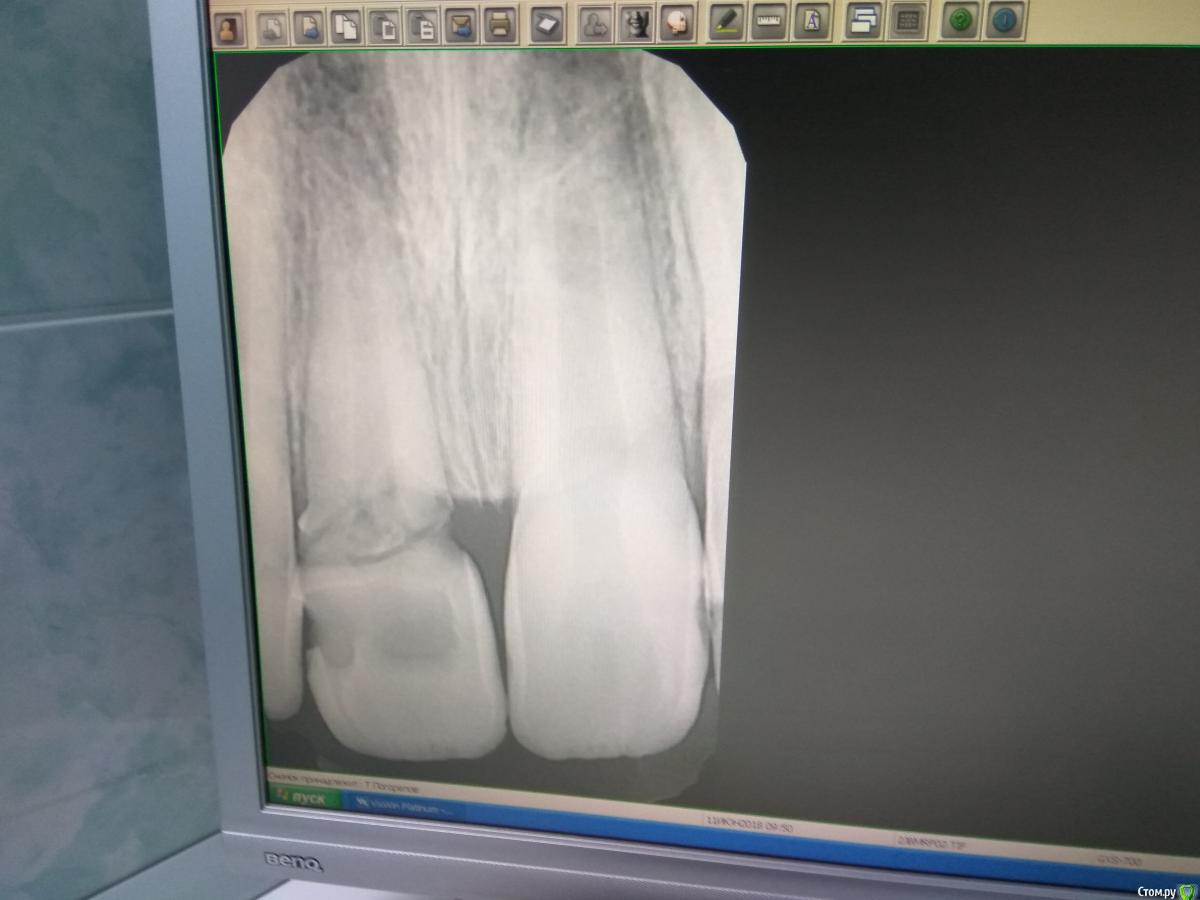

vse32 Опубликовано 3 февраля, 2017 Поделиться Опубликовано 3 февраля, 2017 Лет 8-10 назад у меня такой был. Подвижности ноль. Ортопед прислал на депульпирование. На тот момент - без симптоматики.Так и хранится в баночке, фотала только что на телефон.По-моему близнец вашему.http://s45.radikal.ru/i108/1702/ee/bd70f8a1f08f.jpg Ссылка на комментарий

vse32 Опубликовано 4 февраля, 2017 Поделиться Опубликовано 4 февраля, 2017 А мыть как? Там же гх весь периодонт сожжет. А мыть много, долго, кальций много и долго. Работа бесплатная - за эксперементы денег брать нельзя. Небюджетный эксперимент. Я почему свой зубец сфотографировала- что бы наглядно было видно, насколько велика разруха. Ссылка на комментарий

Давлетшин Опубликовано 6 февраля, 2017 Поделиться Опубликовано 6 февраля, 2017 (изменено) Здравствуйте, да была подвижность. болтался. Я до удаления настраивался на долгое извлечение верхушки, инструменты подбирал, пародонтологические крючки чтоб альеолярный отросток не сносить, а верхушка сама выпрыгнула. Честно хотел оставить, поэксперементировать, думаю даже был бы частичный успех, но пац пришел ко мне после многих которые разводили руками, и всю его веру похоронили. Что скрывать уж лучше удалить, почистить, засыпать лунку, а там и имплант. По фотке, да близнец, только отломана верхняя часть была. Пац сам сказал что что то откусил и что то где то сломалось Изменено 6 февраля, 2017 пользователем Давлетшин Ссылка на комментарий